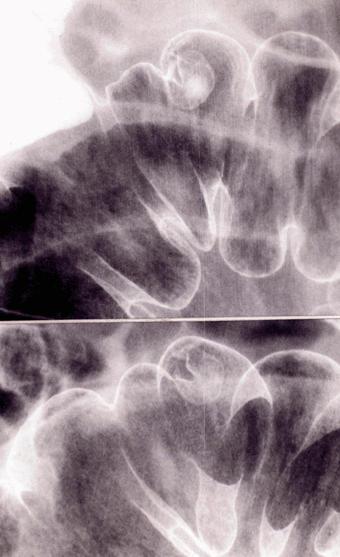

疾患(病理主体)の分類良性上皮性腫瘍/腺腫

部位(臓器別)大腸/S状

検査方法X-P

腫瘍の肉眼分類0型(表在型)/I型(Ip)

病変の最大径(ミリ)15〜19